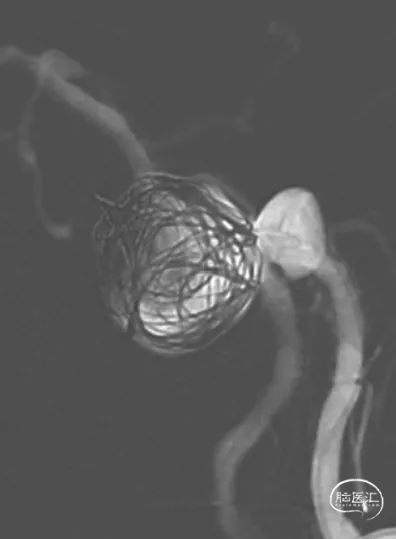

1、基底动脉瘤血流导向装置植入+部分弹簧圈栓塞

3、FRED支架,类型4539(在本病例目标血管里,有效密网长度56mm,支架总长度62mm)

FRED支架释放后,支架CT提示支架贴壁良好

使用25×50、25×50 axium弹簧圈栓塞基底动脉瘤后,使用14×40、10×30、8×30、5×20、3×8 5枚弹簧圈栓塞椎动脉瘤及闭塞左椎动脉末端

经左椎动脉造影,弹簧圈最终完全闭塞左椎动脉V4段,附近的脊髓后动脉保留

经右椎动脉最终造影

术后3个月MRA复查提示:支架内血流通畅,动脉瘤体积进一步缩小。准备6-12月期间复查脑血管造影

2、血流导向装置可以在尽可能保护穿支的前提下,治疗动脉瘤。而少量弹簧圈填充可以促进动脉瘤愈合。

3、患者双侧椎动脉均势发育,一期栓塞左椎动脉瘤及左椎动脉,不会导致严重后循环缺血症状,同时有助于血流导向装置的导流作用,促进基底动脉瘤的愈合。但栓塞椎动脉时,要关注附近的重要血管分支,比如脊髓后动脉。

3、基底动脉瘤内少量弹簧圈填塞,保护动脉瘤相对薄弱区域,纠正载瘤动脉的喷射血流,减少围手术期动脉瘤破裂风险,促进动脉瘤愈合。